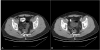

Calcifying fibrous tumor (CFT) is a recently recognized rare benign lesion characterized by dense hyalinized collagenous tissue with interspersed spindle cells and a lymphoplasmocytic infiltrate. Calcification is the hallmark of CFT and may present in the form of psammomatous bodies or dystrophic calcifications. CFT of the intestinal tract is uncommon and rectal CFT has never been reported. Recently, we experienced a case of CFT found in the rectum of a 36-year-old man. In this study, we described the characteristic histopathological findings with a review of the relevant literature. Although CFT of the intestinal tract as an intrinsic visceral lesion is unusual and clinically unexpected, CFT should be considered in the differential diagnosis of rectal submucosal tumor.